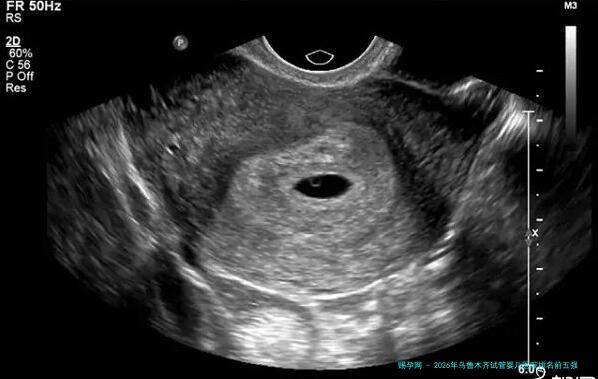

| 乌鲁木齐市妇幼保健院生殖中心 | 1951年建院,生殖中心为重点发展科室 | 公立三级甲等妇幼保健机构,其生殖中心同样具备认证的辅助生殖技术运行资质。 | 位于医院新建大楼内,环境明亮整洁。针对女性患者的特点,服务尤为细致周到。 | 拥有先进的超声影像设备及宫腔镜、腹腔镜等妇科手术配套,为试管周期中的妇科问题处理提供强力支持。 | “主任很有经验,为我制定的方案比较温和,取卵后身体恢复得很快。”(患者刘女士) |